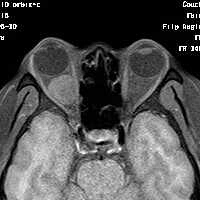

女,54岁,头痛头晕月余,无眼部症状及视力异常。 影像表现:右侧眼球后方占位病变,考虑海绵状血管瘤可能性大,鉴别:视神经鞘瘤、脑膜瘤及炎性假瘤。 病例点评:眼眶内血管瘤是较常见的良性肿瘤,其中以海绵状血管瘤最常见。可发生于任何年龄,主要表现为眼球突出及偏位,在低头或哭泣时可有突眼加重。可经眶缘触及具有压缩性的肿块。视力损害多较缓慢。肿块大多位于肌锥内,其次为肌锥外,平扫呈边界清楚的圆形、卵圆形或分叶状肿块,增强扫描呈缓慢进行性显著强化为其特征性表现。